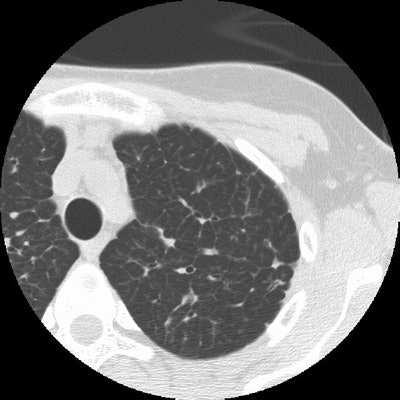

Sarcoid Stage 4:

The case below in from a patient with a history of sarcoid. The HRCT examination demonstrates interstitial lung disease with peripheral traction bronchiectasis that has been stable over the past several years. (Click image to enlarge)